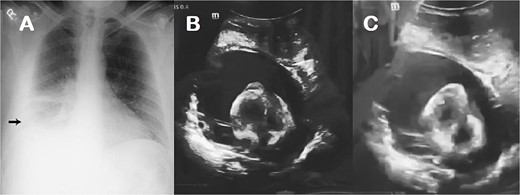

A 2-year-old female patient with no known medical history presented with tachycardia, respiratory distress, hepatomegaly, jugular engorgement, and muffled heart sounds suggestive of cardiac tamponade, with effacement of the costophrenic angles and a cardiothoracic index of 0.66 on chest X-ray. An echocardiogram confirmed significant diffuse pericardial effusion, with an anterior layer measuring 24 mm and a posterior layer measuring 77 mm, with a right pleural effusion (Fig. 1), and with hemodynamic repercussions. We performed subxiphoid pericardial drainage, obtaining 550 ml of serosanguineous characteristics with moderate amounts of loose tissue and showing thickening of the pericardium. Cytochemical analysis indicated exudate results with no bacterial growth in the fluid culture and pericardial tissue, after which the patient remained in the intensive care unit for 7 days. Before removing the pericardial drainage tube, we performed a new echocardiogram, showing little residual fluid, after which the patient was discharged home.

Chest X-ray (A) and echocardiogram (B & C) with evidence of pleural and pericardial effusion.